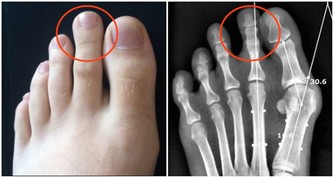

公司職員顧小姐由於工作壓力過大,出現了失眠的情況,在網上看到音樂可以治療失眠,於是她每天晚上睡覺前都戴上耳機聽一陣子音樂,常常是MP3還在放著音樂,她卻已經睡著了。沒過多久,她就發現自己的耳朵開始有鳴音,聽東西也時常不清楚,要別人重複很多遍。後來發展到全身的神經系統都出現異常症狀,經常頭暈頭痛,難以忍受,甚至耳朵一碰就痛,嚴重影響到她的學習和生活。經過醫生的音叉檢查和純音測試,發現她的聽力已經比常人下降了40分貝。

酷愛流行音樂的曉曉只要不是在上班,那耳朵裡一定塞著耳機。尤其在逛街、坐公交車等聲音嘈雜的場合,她都會不自覺地把聲音調高。晚上回到家中看電視時,聲音總是開得很大,自己還渾然不覺。直到有一次媽媽出來問她:「這麼大的聲音,像在電影院一樣,你耳朵吃得消嗎?」。在一次體檢中,經醫生過診斷,她的鼓膜完整、中耳無感染,聽力測試後確診為感音神經性耳聾,聽力衰退程度已經很嚴重。